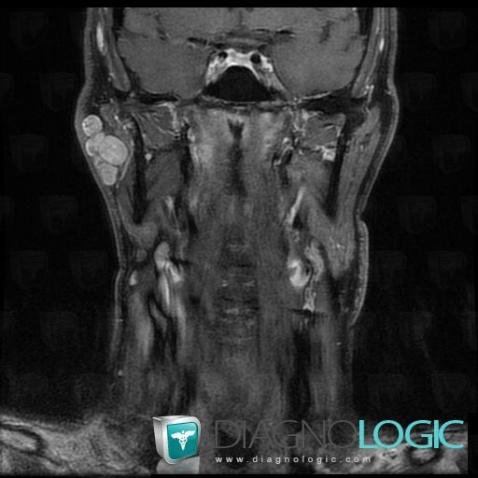

Pleomorphic adenoma, Parotid and other salivary glands, MRI

Here is the specific information in the key image above:

- Diagnosis Pleomorphic adenoma, Location(s) Parotid and other salivary glands, with gamuts Parotid gland lesion / enlargement, Neoplasic parotid gland lesion, Multiples parotid gland lesions